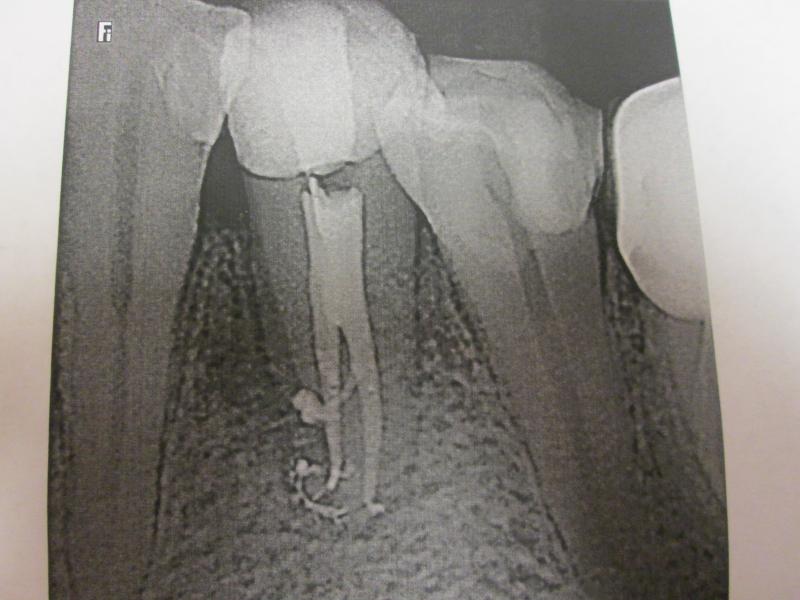

DR JET LOVES ROOT CANALS

General Dentist,  Performs Root Canals ONLY - Microscope Trained Dentist

"DR. JET'S MISSION IS TO PERFORM  ROOT CANALS FOR A REDUCED FEE USING THE LATEST TECHNOLOGY  AND TECHNIQUES TO SERVICE THE MANY PEOPLE WHO ARE UNINSURED OR UNDER-INSURED GIVING EVERYONE AN OPPORTUNITY TO SAVE THEIR TOOTH!"

**PLEASE BE AWARE THAT  A ROOT CANAL IS AN ATTEMPT TO SAVE YOUR ALREADY DAMAGED TOOTH.  THERE IS NO GUARANTEE THAT ANY TOOTH CAN BE SAVED BUT DR JET WILL DO HIS BEST TO HELP YOU. THE OTHER OPTION IS TO EXTRACT YOUR TOOTH

ROOT CANALS by DR. JET (Jetepon Chiranand DDS)